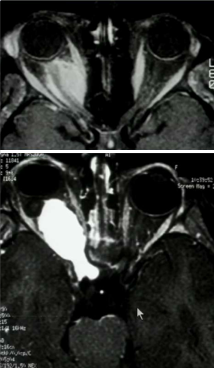

What is your diagnosis?

Note that the patient’s left optic nerve is brighter (enhanced by gadolinium), which is abnormal because it does not have a BBB. The size of CN II is normal so the patient has optic neuritis.

CN II is a part of the brain, so it is an optic nerve glioma.

What is your diagnosis in each of these patients?

The patient on top has an optic meningioma (non-enchancing nerve surrounding by enhancing mass). The patient on bottom has an optic glioma (entire nerve enhancing).